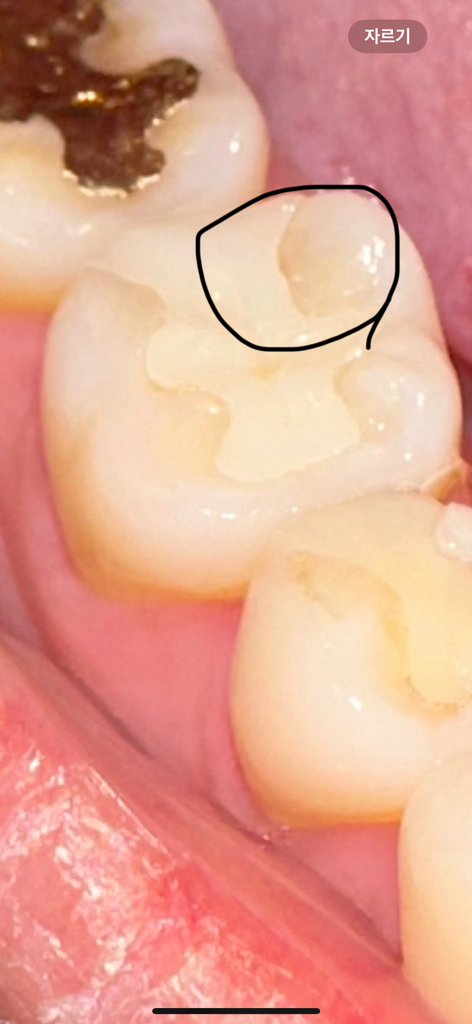

음식물이 해당 부위로 끼는 등 아주 불편하다면 보철물 교체를 고려해볼 수도 있으나 현재로선 특별히 증상이 없고 충치의 양상도 아니라고 판단되기 때문에 굳이 교체를 권유하진 않는 것 같습니다.

인레이 보철물의 틈이 있다면 다듬거나 할 수 있습니다. 치아의 틈이 넓어서 해당 부위에 문제가 생길 가능성이 있다면 보철물을 교체해 주는 것이 좋을 수 있습니다.